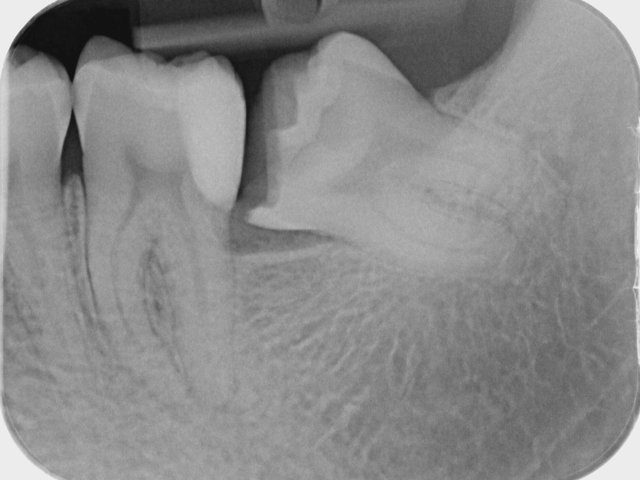

Verlagerung und Retention

Tiefe Karies wegen eines benachbarten Weisheitszahnes

Tiefe Karies wegen eines benachbarten Weisheitszahnes ...